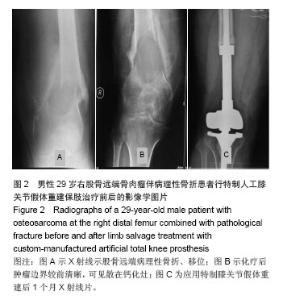

Application of custom-manufactured artificial total knee prosthesis in limb salvage surgery for patients with a pathologic fracture in osteosarcoma

METHODS: A total of 11 patients with pathological fracture with osteosarcoma located in adjacent knee Joint were enrolled from June 2002 to September 2012. In accordance with individual condition of the patient, limb salvage treatment was designed for knee prosthesis for a tumor. Follow-up results were retrospectively analyzed. There were six males (54.5%) and five females (45.5%) and their age ranged from 11 to 50 years old with an average age of 25.4 years old. Onset regions: seven tumors were located in the distal femur and four tumors were in the proximal tibia. All patients received neoadjuvant chemotherapy, and limb salvage treatment with custom-manufactured artificial knee prosthesis. The follow up was performed for 9 to 105 months.

RESULTS AND CONCLUSION: In 11 patients after prosthesis replacement, the regional recurrence rates were 18%, lung metastasis rates were 36%. The five-year survival rate was 58%. Four patients developed lung metastases and died in 9 to 24 months postoperatively. During the last follow-up, Enneking score of the affected limbs was 11 to 30 points, averagely 23.3 points, with an excellent and good rate of 82%. Results indicated that combined with neoadjuvanet chemotherapy, the application of custom-manufactured artificial total knee prosthesis replacement in the treatment of osteosarcoma located in adjacent knee joint and pathological fracture achieved an ideal outcomes of the limb salvage treatment in the near future. The lone-term effectiveness was expected to be evaluated.